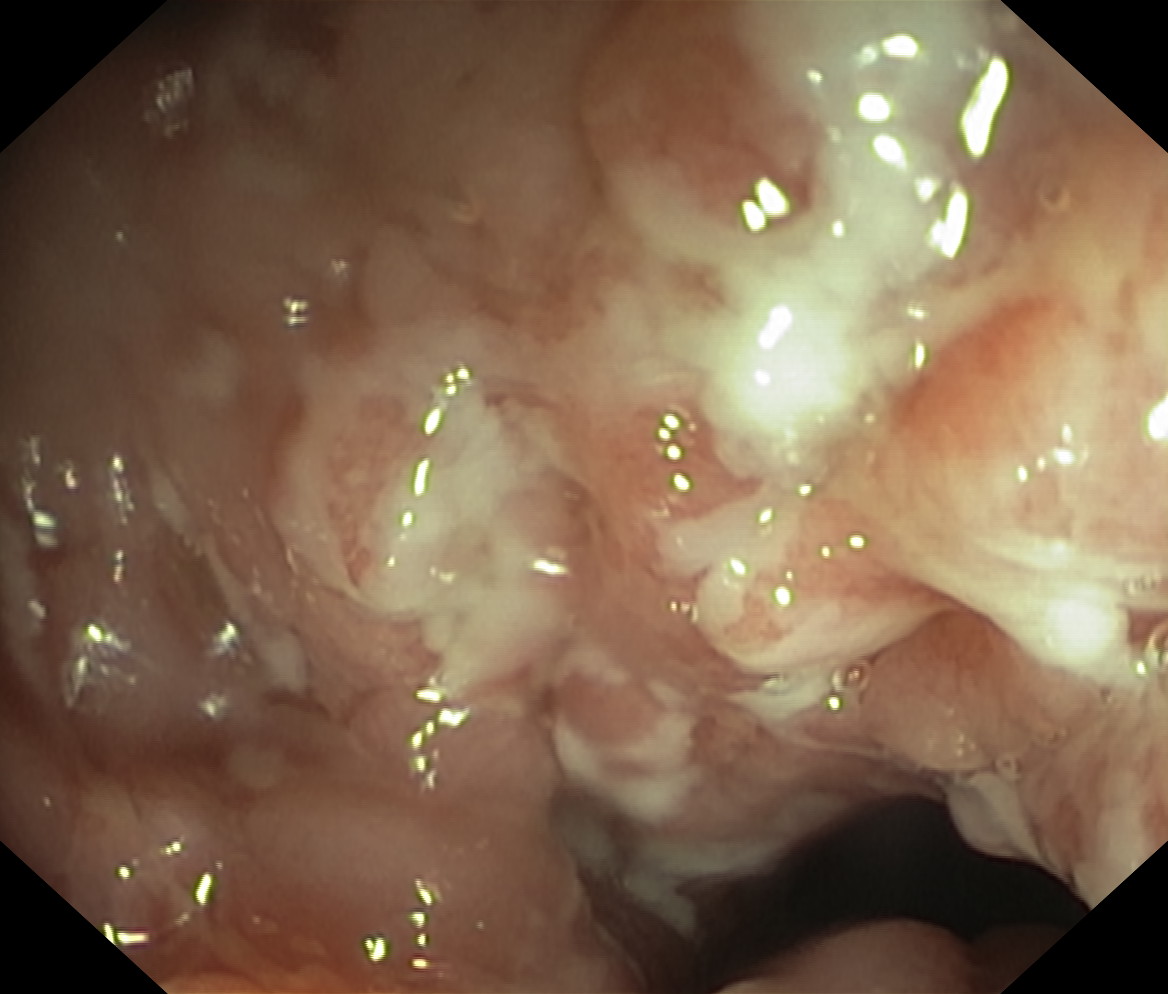

Choroba Leśniowskiego-Crohna